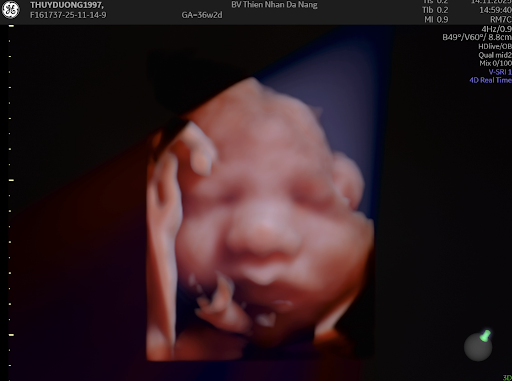

Dưới đây là một số hình ảnh thực hiện siêu âm, tầm soát tại khoa phụ sản:

Bao gồm khám phụ khoa, khám thai định kỳ, siêu âm thai 4D, sàng lọc trước sinh, tầm soát ung thư phụ khoa,… đảm bảo chăm sóc toàn diện cho sức khỏe phụ nữ.

Trang bị hệ thống máy móc hiện đại như siêu âm 4D, MRI khung chậu, nhũ ảnh 3D,… giúp đánh giá chính xác tình trạng sức khỏe và đưa ra phác đồ phù hợp.